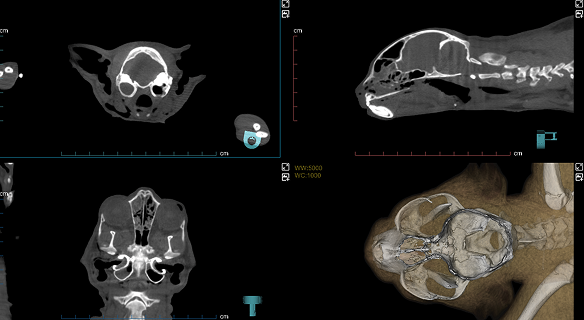

Imágenes Clínicas